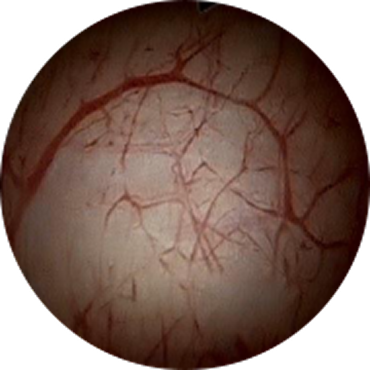

간질성 방광염

구상화 병변

구상화 병변간질성 방광염